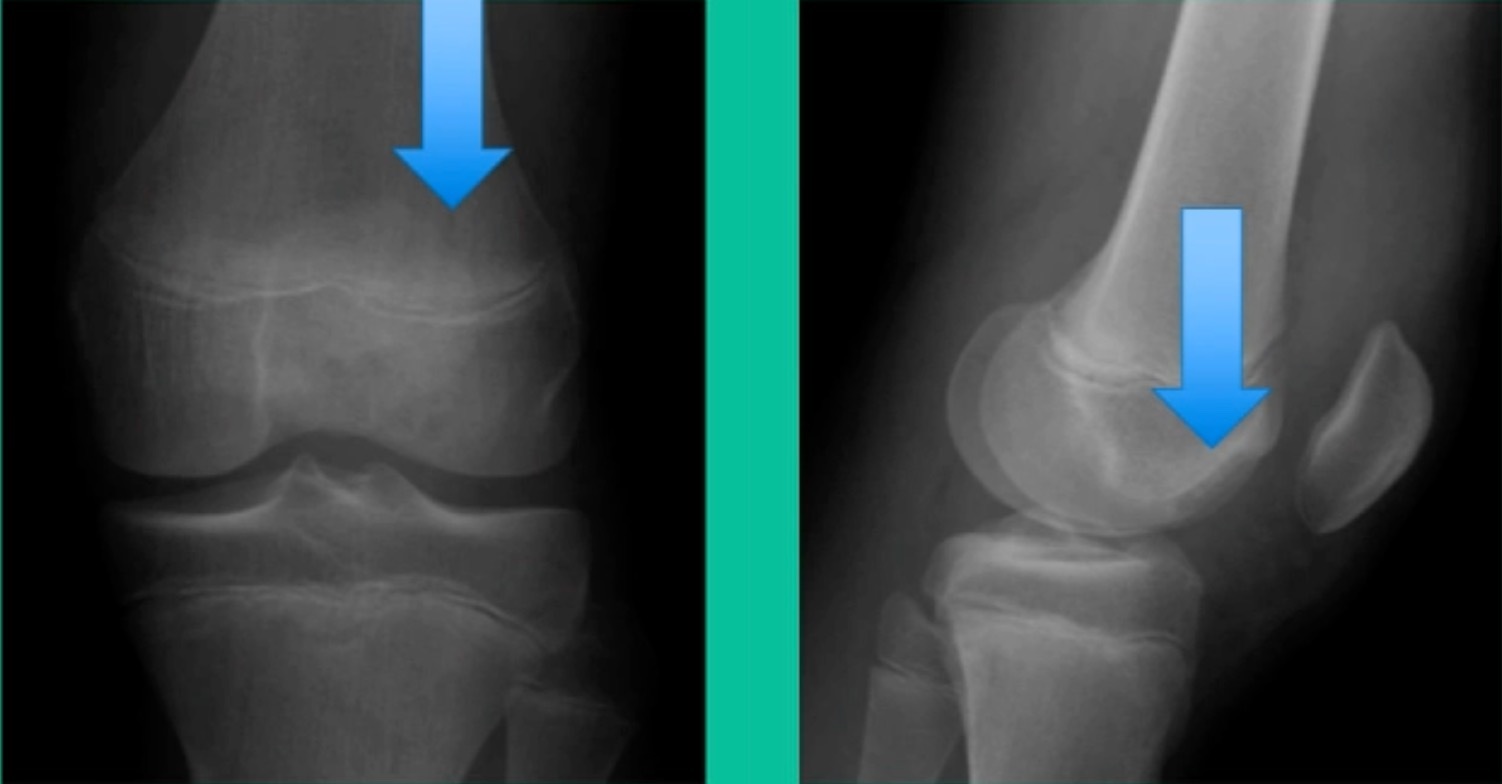

Now, we’ll shift to the adult. This is a 27-year-old. Right knee swelling, activity-related, and classic failed nonsurgical treatment on the lateral side of the knee.

This will probably be fixed. It’s a big piece and we’ll try to preserve it. The literature shows that preservation does pretty well. In this instance, there’s very little bone. It’s somewhat dystrophic, not very encouraging in my mind.

43-Year-Old, symptomatic medial femoral condyle.

D1 football player formally, affecting ADLs. For this one, I initially just wanted to watch it. This looks pretty small when he came in. Let’s see what happens. Six months later, this is where he progressed to.

This is an 18-year-old with a lateral femoral condyle OCD:

Worsening over the last two years, has effusions but no locking, and has a large area of involvement that appears unstable. This is the classic fixation. If you can do this, this is the holy grail. Remember, fracture non-union: you elevate it, debride the base, get rid of any unstable fragments, just take them out, and preserve the major fragment. I’ll use a microfracture awl, but most commonly now I’ll use a pick or a pin, and I’ll drill it. I use two to three metal screws. I bury their heads, and then I come back at eight weeks after being non-weight-bearing, and pull the screws out.